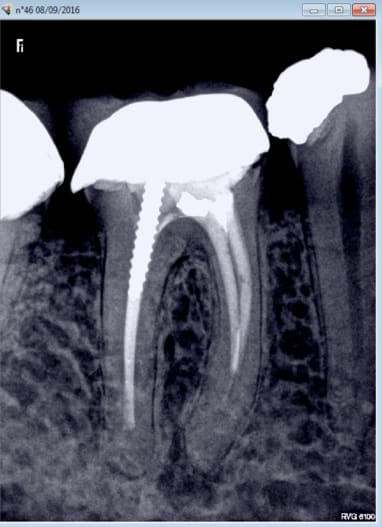

C'est rien ca, je te présente des travaux conforme aux tarifs de la grande sécurité sociale française d'un praticien qui gagne bien sa vie

Nb : le oatient venait car le bridge secteur 3 se casse la gueule : IC de 0.1 mm (sans blague), et couronne pas aux limites (qui sont de toute façon pas taillées)